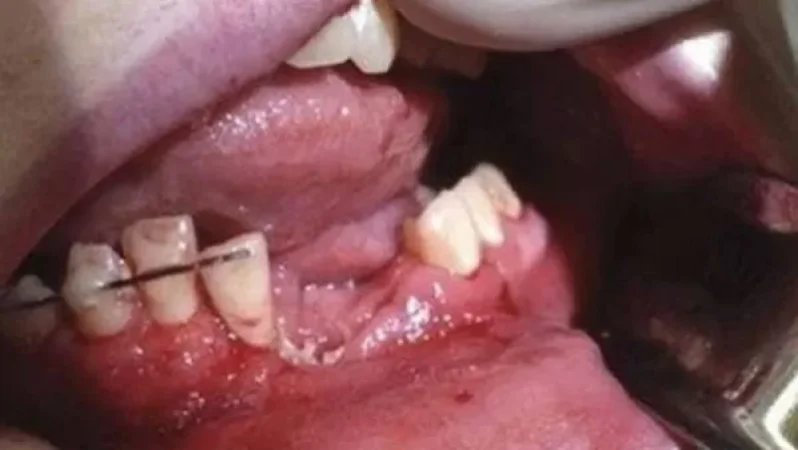

«Երբ էլեկտրոնային, այսպես կոչված, նորարարական ու տաքացվող ծխախոտը պայթում է ձեռքիդ մեջ և դու ունենում ես կոտրված ծնոտ կամ խեղված ձեռք։

Այս դեպքը տեղի է ունեցել 17-ամյա դեռահասի հետ»,- այս մասին ֆեյսբուքյան իր էջում գրել է ՀՀ առողջապահության նախարար Արսեն Թորոսյանը։